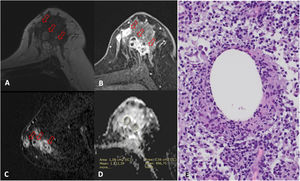

Mastitis granulomatosa idiopática en una paciente de 42 años. A) La ecografía mostró pseudoquistes menores de 1cm en la mama derecha. B) Imagen de RM en T2 que muestra múltiples nódulos menores de 1cm hiperintensos (flechas). C) Imagen de RM poscontraste, T1 con saturación grasa y sustracción, muestra captación de tipo no masa con distribución regional y patrón en anillos agrupados que se relacionan con los nódulos hiperintensos en T2 y corresponden a microabscesos. D) El mapa de CDA muestra uno de los 3 valores estudiados, cuyo promedio fue 1,352×10-3mm2/s.

Mastitis granulomatosa idiopática en una paciente de 27 años. La ecografía mostró áreas hipoecogénicas irregulares en la mama derecha que asociaron señal Doppler (no mostrado). A) Imagen de RM T2 que muestra extensas áreas discretamente hiperintensas y engrosamiento cutáneo focal con trayecto fistuloso asociado (flecha). B) Imagen de RM poscontraste, T1 con saturación grasa y sustracción, muestra un realce de tipo no masa de 94mm con una distribución regional y patrón en anillos agrupados (flechas). C) La imagen en proyección de máxima intensidad de contraste muestra la extensa afectación inflamatoria que ocupa los cuadrantes superiores de la mama derecha. Nótese el grosor de piel normal en la mayor parte de la mama, excepto el área del trayecto fistuloso (flecha en A). D) Se estudiaron 3 valores de CDA cuyo promedio fue 0,965×10-3mm2/s.

Mastitis granulomatosa quística neutrofílica en una paciente de 36 años. La ecografía mostró múltiples nódulos hipoecogénicos que asociaron señal Doppler (no mostrado). A) Imagen RM en T2 que muestra nódulos hiperintensos (flechas). B y C) Imágenes de RM poscontraste, T1 con saturación grasa (B) y reconstrucción sagital en sustracción (C), que muestran un realce de tipo no masa con distribución en múltiples regiones y patrón en anillos agrupados (flechas). D) Se estudiaron 3 valores de CDA cuyo promedio fue 1,221×10-3mm2/s. E) La anatomía patológica muestra presencia de histiocitos epitelioides formando un granuloma no necrotizante con un espacio quístico central y presencia de neutrófilos a su alrededor en un contexto inflamatorio de predominio linfoplasmocitario (20×). La PCR para Corynebacterium kroppenstedtii fue positiva.